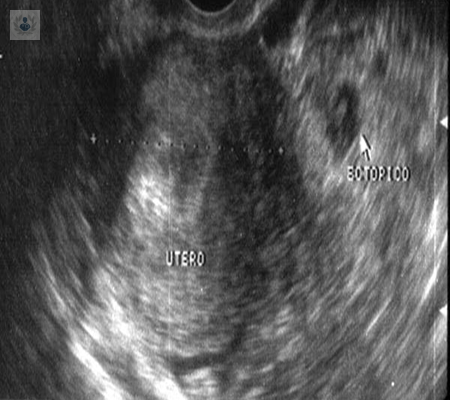

Causas y síntomas de un embarazo ectópico

En un embarazo normal, un óvulo fecundado se implanta y crece dentro del útero. En un embarazo ectópico, el óvulo fecundado no llega al útero y se queda en otra cavidad del cuerpo.

Embarazo Ectópico

Los principales signos que se presentan son dolor abdominal o pélvico y sangrado vaginal. El embarazo ectópico se debe sospechar en cualquier mujer en edad reproductiva.